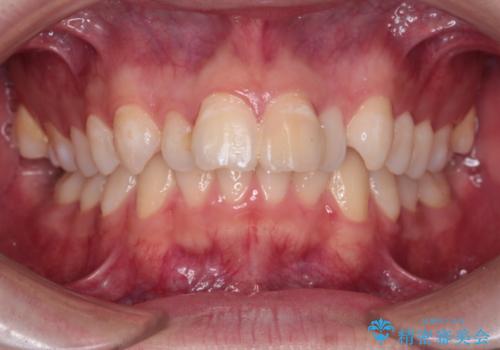

- 前歯が出ていることを主訴に来院されました。

臼歯関係が上顎前突傾向のため、上顎小臼歯を抜歯してインビザラインにて治療を行いました。